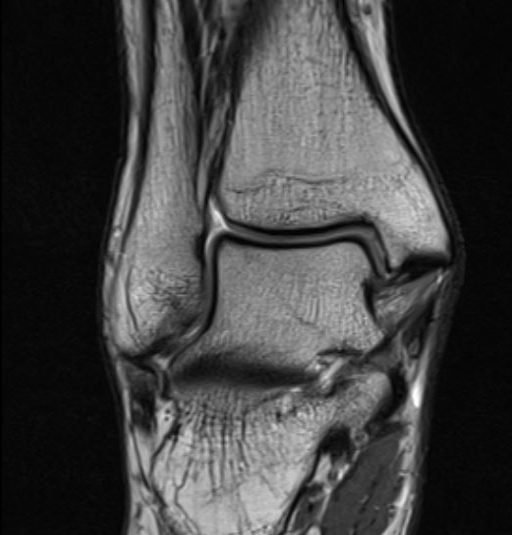

MRI

Tear of AITFL / intact PITFL

Tear of AITFL, intact PITFL, and syndesmotic injury with external rotation of the fibula

Tear of AITFL & PITFL with syndesmotic widening